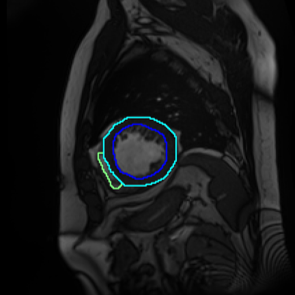

Figure 1: Different sections of a heart. (a) represents the basal section, which lacks regions of the right ventricle(RV), myocardium, and the left ventricle(LV); (b), (c), and (d) approach the apical section, while the RV, myocardium, and LV vary in size and shape.

French et al.[13] emphasized that consistency regularisation requires robust and diverse perturbations in semantic segmentation, which leads networks to possess a strong ability to generalize. Perturbations are usually performed using a set of data augmentation algorithms, and consistency regularization uses highly augmented images to efficiently learn unlabelled data. In terms of the intricate anatomical shapes in greyscale medical images, data augmentation algorithms should be able to enable the segmentation model to identify the shapes of objects, especially contours. Furthermore, medical images sometimes do not contain objects from some specific classes, which can lead to inter-class imbalance (Figure 1). To address these challenges, we introduce Scaling-up Mix with Multi-Class (SM22{}^{2}start_FLOATSUPERSCRIPT 2 end_FLOATSUPERSCRIPTC), a novel data augmentation algorithm based on image mixing techniques to generate a more diversified training dataset. Targeting the primary tasks of semantic segmentation - region and contour recognition - our algorithm processes the shapes of segmentation objects and merges semantic features from multiple original images into a novel composition. We incorporate the method into a pseudo-labeling framework to improve the teacher model’s ability to learn unlabeled data and conduct experiments on three medical image datasets.